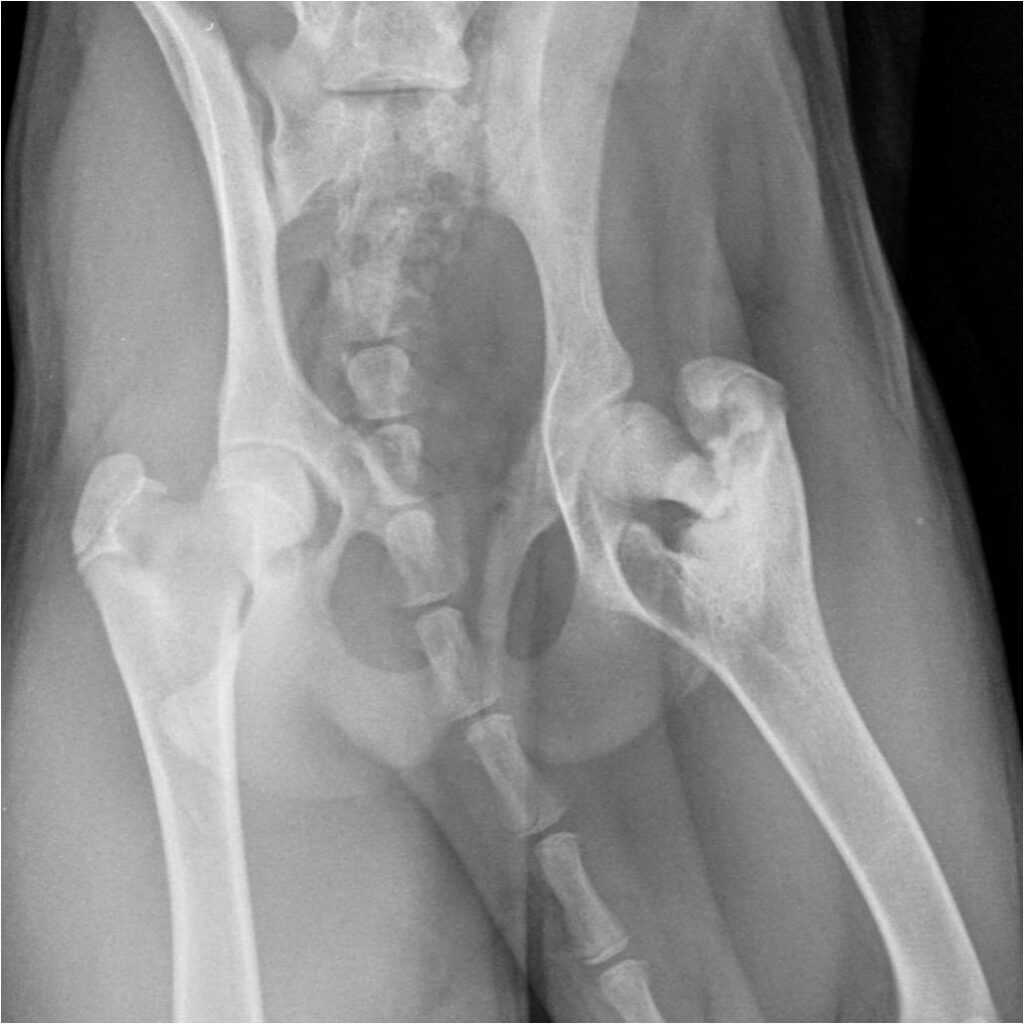

Тяжелая форма болезни Пертеса

Рентген бедра может предложить и / или подтвердить диагноз. На рентгеновских снимках обычно выявляется уплощенная, а затем фрагментированная головка бедренной кости. Сканирование костей или МРТ может быть полезно при постановке диагноза в тех случаях , когда рентгеновские лучи не являются окончательными. Обычно простые рентгенологические изменения откладываются на 6 недель или более от начала клинического заболевания, поэтому для ранней диагностики проводят сцинтиграфию костей и МРТ. Результаты МРТ более точны: от 97 до 99% против 88-93% при простой рентгенографии. Если необходимы МРТ или сканирование костей, положительный диагноз основывается на пятнистых участках кровоснабжения эпифиза верхней части бедренной кости (развивающейся головки бедренной кости). необходима цитата

Основным исследованием выступает рентген

При его проведении очень важно сохранять неподвижность, поэтому животному делают общий наркоз или седацию. На основании полученного снимка ветеринар определяет не только сам факт патологии, но и ее стадию.

На рентгенографическом изображении хорошо видны как первоначальные признаки болезни, так и более поздние. В первом случае снимок покажет уплотнение костной ткани и изменение формы головки бедра, а во втором видны костные разрастания на головке, остеоартроз, а в самом тяжелом случае — перелом шейки бедра или ее разрушение.